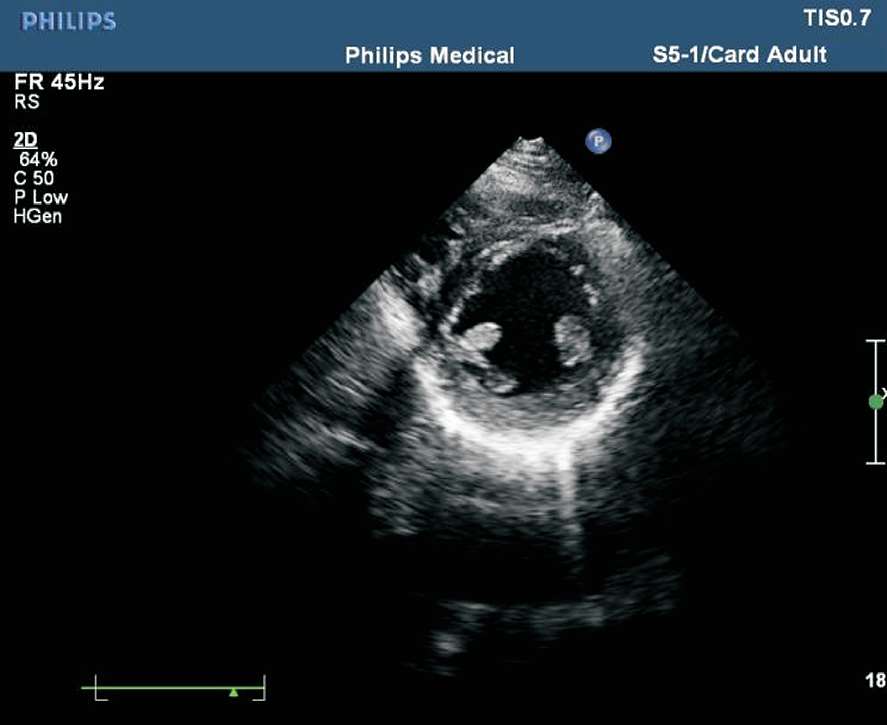

患者取左侧卧位或平卧位,探头置于胸骨左缘第2~3 肋间,声束垂直于胸骨旁左心室长轴切面。在此切面可观察主动脉瓣的形态、厚度、回声强度及开闭状态,右心室流出道与肺动脉干有无增宽、狭窄,降主动脉与肺动脉之间有无异常通道,肺动脉瓣的形态及活动(见图1-27)。正常主动脉瓣呈三瓣叶,收缩期开放为“▽”形,舒张期关闭为“Y”形(见图1-28)。

图1-28 心底大动脉短轴切面主动脉瓣呈三瓣叶,舒张期关闭为“Y”形